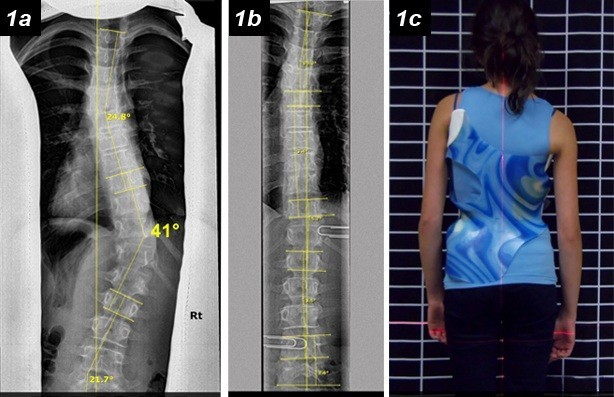

التنبؤ بنتائج حزام اعوجاج العمود الفقري :الفرق بين الأشعة داخل الحزام وخارجه…

التنبؤ بنتائج حزام اعوجاج العمود الفقري :الفرق بين الأشعة داخل الحزام وخارجه يُعد اعوجاج العمود الفقري عند المراهقين من أكثر حالات التشوهات الشائعة خلال مرحلة النمو، ويُعرف طبيًا باسم “الجنف مجهول السبب عند المراهقين”.